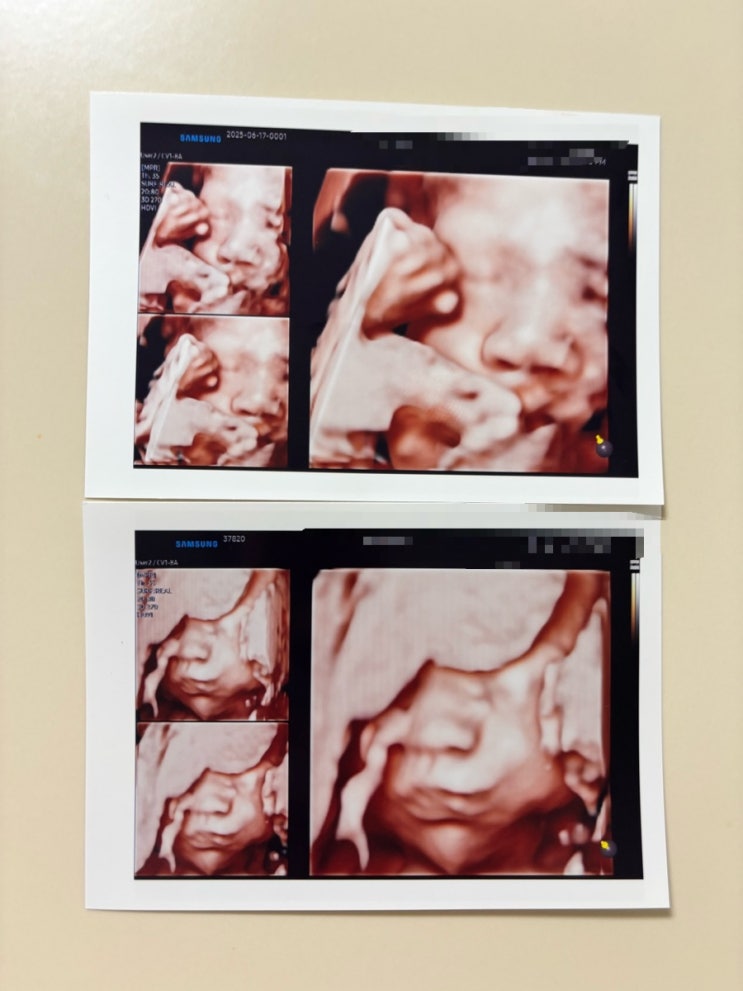

30주임산부일상일기 백일해 입체초음파

30주차 증상 잦은 배뭉침 새벽에 3번 이상 깨면서 종일 피곤 속쓰림 유선발달로 인한 가슴 통증 겨드랑이 ...